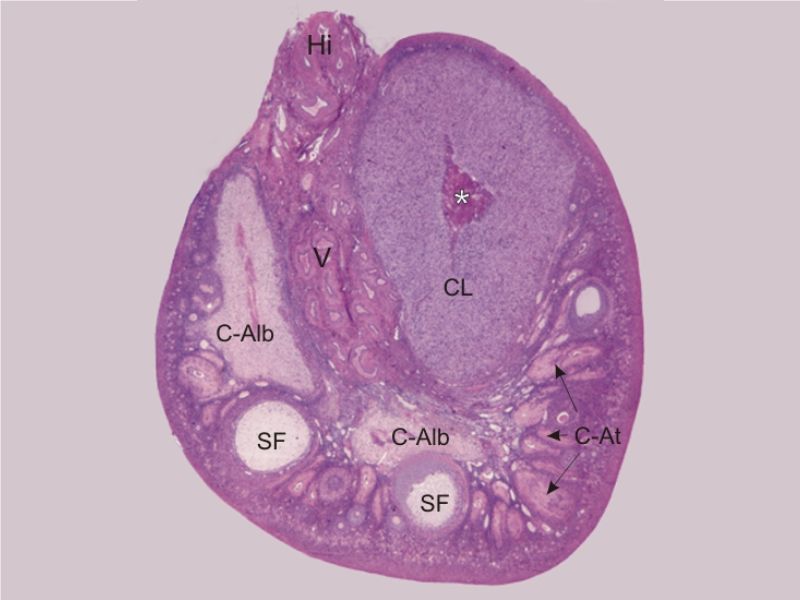

Ovaries

Slide 24

Section of the ovary

Ovary

- Capsule covered by modification of peritoneum

- Called germinal epithelium

- Simple squamous/cuboidal

- Subdivided

- Not clearly defined

- Cortex - contains ovarian follicles

- Medulla - vascular

Germinal epithelium

- Misnomer

- NOT source of primary follicles

- Cover capsule

- Simple squamous/cuboidal epithelium

Cortex

- Tunica albuginea

- Irregular dense CT capsule

- Follicles in various phases

- Stroma containing follicles

Stroma

- Highly cellular loose CT

- Fibroblasts

- Elastic & collagen fibres

- Form layers around follicles

Medulla

- Blood vessels

- Hilus cells

- Stroma

Blood vessels

- Enter medulla at hilus

- Supply the cortex

- Epithelioid cells clump around blood vessels

Epithelioid cells

- Located in hilus

- Also called hilus cells

- Clump around blood vessels

- ≈ Leydig cells

- Probably produces androgens

Corpus luteum

Slide 91

Corpus luteum

- Two major cell types

- Granulosa lutein cells

- modified granulosa cells

- Theca lutein cells

- modified theca interna cells

- Many capillaries

Granulosa lutein cells

- Modified granulosa cells

- Large - 30µm

- Pale cells

Theca lutein cells

- Modified theca interna cells

- Smaller - 15µm

- Dark stained